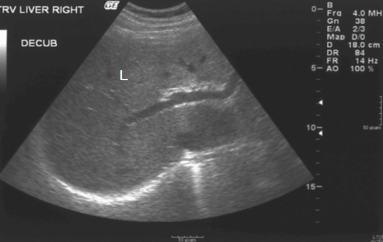

What is the echogenicity of the mass in the liver?

Hypoechoic